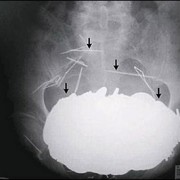

Батерии